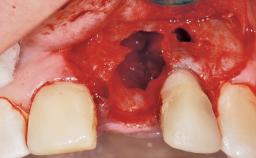

A 30-year-old female patient had lost tooth 21 and was referred to our clinic for consultation and treatment. Due to advanced apical infection, tooth 21 had been extracted two months earlier at another clinic and an acrylic-resin tooth had been bonded to the adjacent teeth. The patient desired implant treatment to avoid any damage to the adjacent natural teeth. While the patient had no history of any systemic disorder, she was a heavy smoker and exhibited medium to advanced periodontitis in the entire jaw. After the initial treatment to achieve a pocket probing depth of less than 4 mm and no bleeding on probing, a decrease in the height of the papillae mesial and distal to the extraction site and overall gingival recession were observed.

Bone Augmentation Horizontal|Staged

Augmentation Materials Autogenous chips|Membrane

Soft Tissue Grafting Simultaneous

Soft Tissue Anatomy Intact Defective

Bone Volume Horizontally and vertically sufficient Horizontally deficient Deficient vertically or deficient vertically AND horizontally

Bone Volume Deficient horizontally, requiring prior grafting